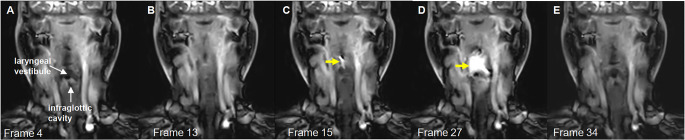

Cine magnetic resonance imaging (Cine-MRI) may evaluate the swallowing function and locations of patients with dysphagia, which requires very fast imaging speed. Compressed sensing is a technique that allows for faster MRI imaging by sampling fewer data points and reconstructing the image via optimization techniques, crucial for capturing the rapid movements involved in swallowing. This study aimed to analyze swallowing function and locations in patients with head and neck cancer and healthy individuals using Cine-MRI based on compressed sensing. This comparative study enrolled 36 patients with dysphagia and 10 healthy controls at the Department of Radiology, Yunnan Cancer Hospital between June 2020 and January 2021. Significant correlations were found between primary tumor location and Cine-MRI parameters, and between swallowing function and Cine-MRI parameters. The areas under the receiver operating characteristic curve for the combined Cine-MRI-related parameters in predicting mild and severe dysphagia were 0.806 (95% CI: 0.662-0.949). Cine-MRI with compressed sensing may identify swallowing function and abnormal stages of the physiologic swallowing process in patients with dysphagia after treatment.